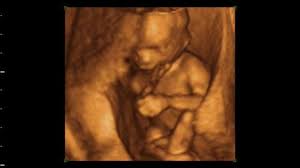

3d Ultraschall Bei 19 0 20 Ssw Youtube

3d Ultraschall Bei 19 0 20 Ssw Youtube from i.ytimg.com